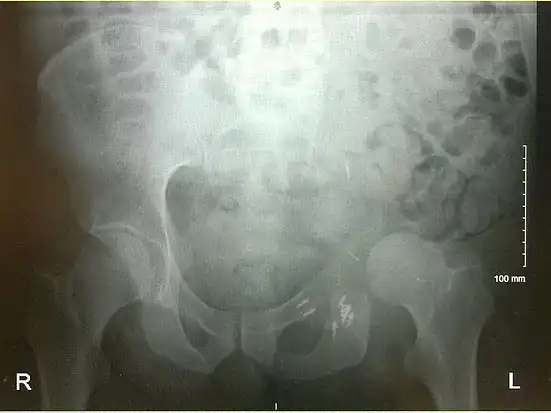

An x-ray of the same pelvis taken eighteen months after surgery highlighting the femur migration to its final resting place.